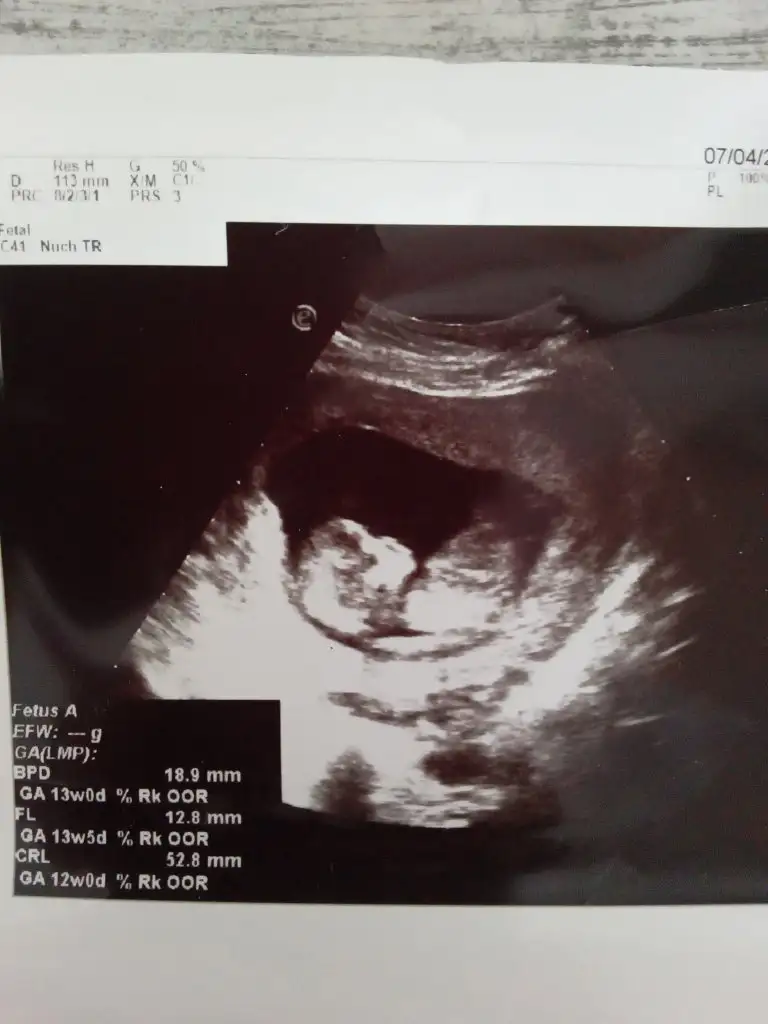

12 haftalik karindan cekildi 1 hafta onde gidiyor 13 cikti olcumlerde ne olaki cinsiyetimiz merak ediyorum cok

8+2 hamilelik tahmininiz nedir

Eklentiler

• 5C584AE7-1DDF-4CBD-ADC5-4DFB1F7D15B6.webp

24,8 KB · Görüntüleme: 64